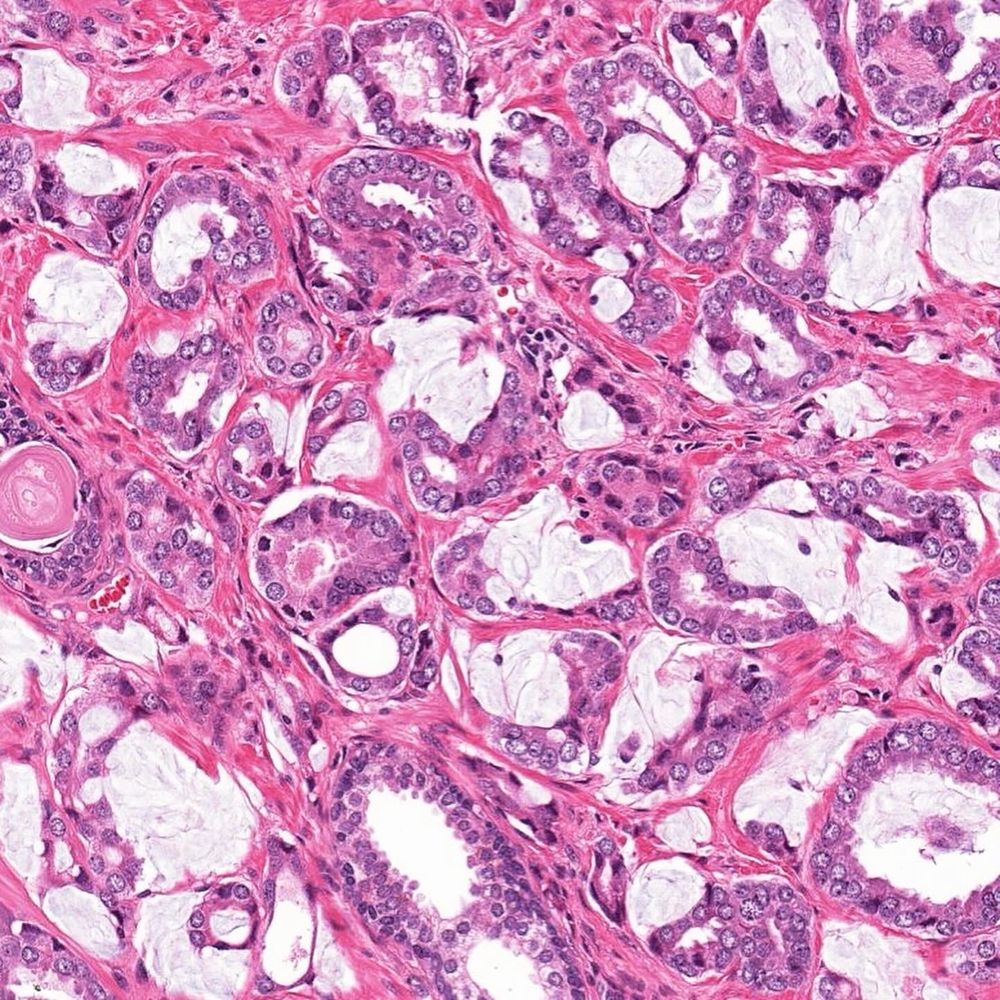

#slidearchiveseries renal oncocytoma #gupath

🔬solid-nested growth, edematous stroma

🎨 CD117 positive, CK7 negative or scattered single/small clusters of positive cells, Hale collodial iron negative (apical luminal positivity may be seen)